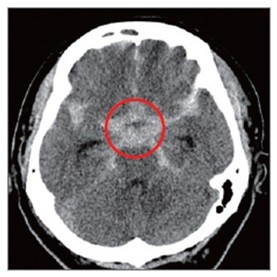

뇌동맥류로 인해 부풀어 오른 혈관이 터지면 뇌출혈이 생긴다. 이 경우 사망 위험이 크게 증가하고 뇌에 영구적 손상이 가해져 언어장애, 운동장애 등이 유발된다.

뇌동맥류 파열은 혈압으로 인한 뇌압 상승이 주 원인이다. 따라서 혈압에 영향을 미치는 고혈압, 당뇨병, 고지혈증 등의 질환이 위험인자가 될 수 있다. 혈압을 높이는 음주, 비만, 흡연 등의 생활습관도 마찬가지다. 또한 갑자기 무거운 물건을 들거나 힘을 줘서 대변을 보는 등 혈압을 높이는 행동도 뇌동맥류 파열 위험을 높인다. 같은 이유로 격렬한 운동, 기침 등도 위험인자가 될 수 있다.